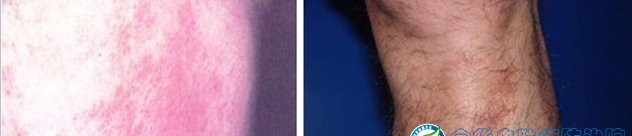

二、日光性皮炎